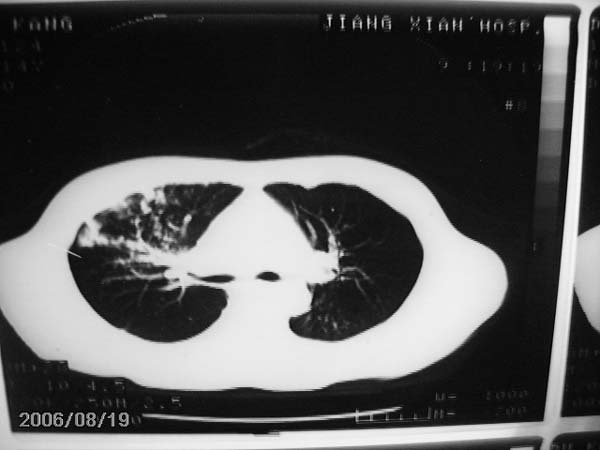

男,13岁,发烧半月,干咳无痰,正规使用抗生素半月,现在仍是午后低烧!!!未做痰检

右肺中叶大片状密度增高影,内密度不均匀,右肺门处增大,应该是淋巴结肿大,结合临床首先考虑原发性肺结合可能性大,不排除合并感染可能,建议治疗后复查.

灶内密度不均,似乎有囊状,条状影,考虑右中叶综合症; 从照片中看不出有无钙化灶,若明显则考虑结核性。

考虑中叶综合征(右肺门肿大淋巴结伴中叶阻塞性炎症)